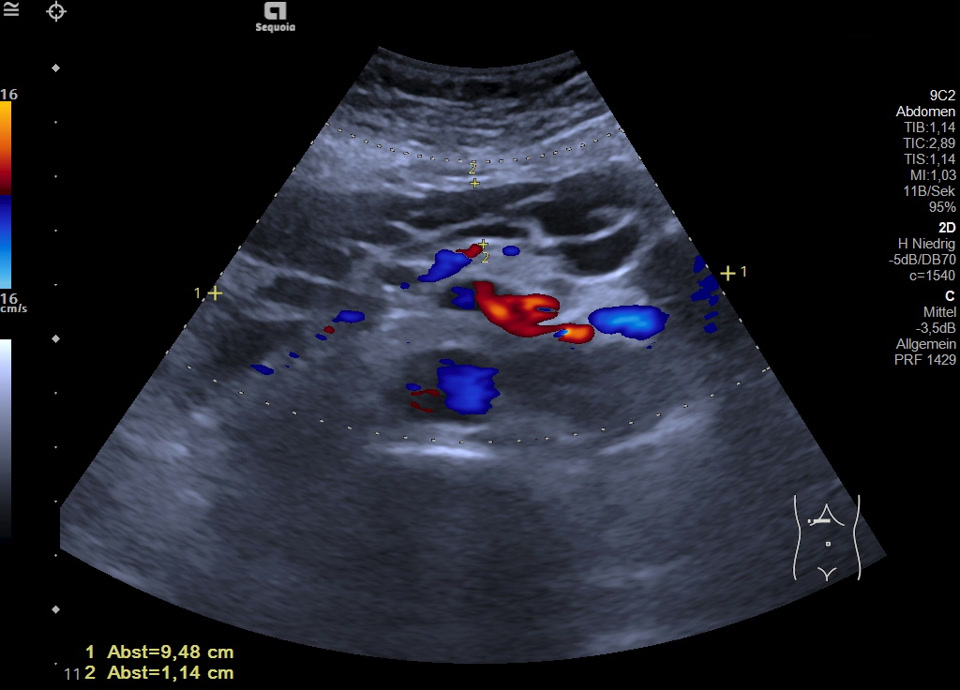

Lymphgefäße

• Lymphangiom (Video)

• Lymphangiom (Farbdoppler)